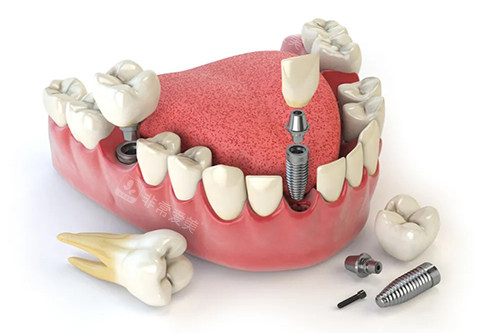

牙齿种植卡通示意图

在牙齿修复方面,无论是常见的补牙、镶牙,还是较高的种植牙技术,都能为患者提供个性化的方案,帮助患者修复牙齿的功能和美观。